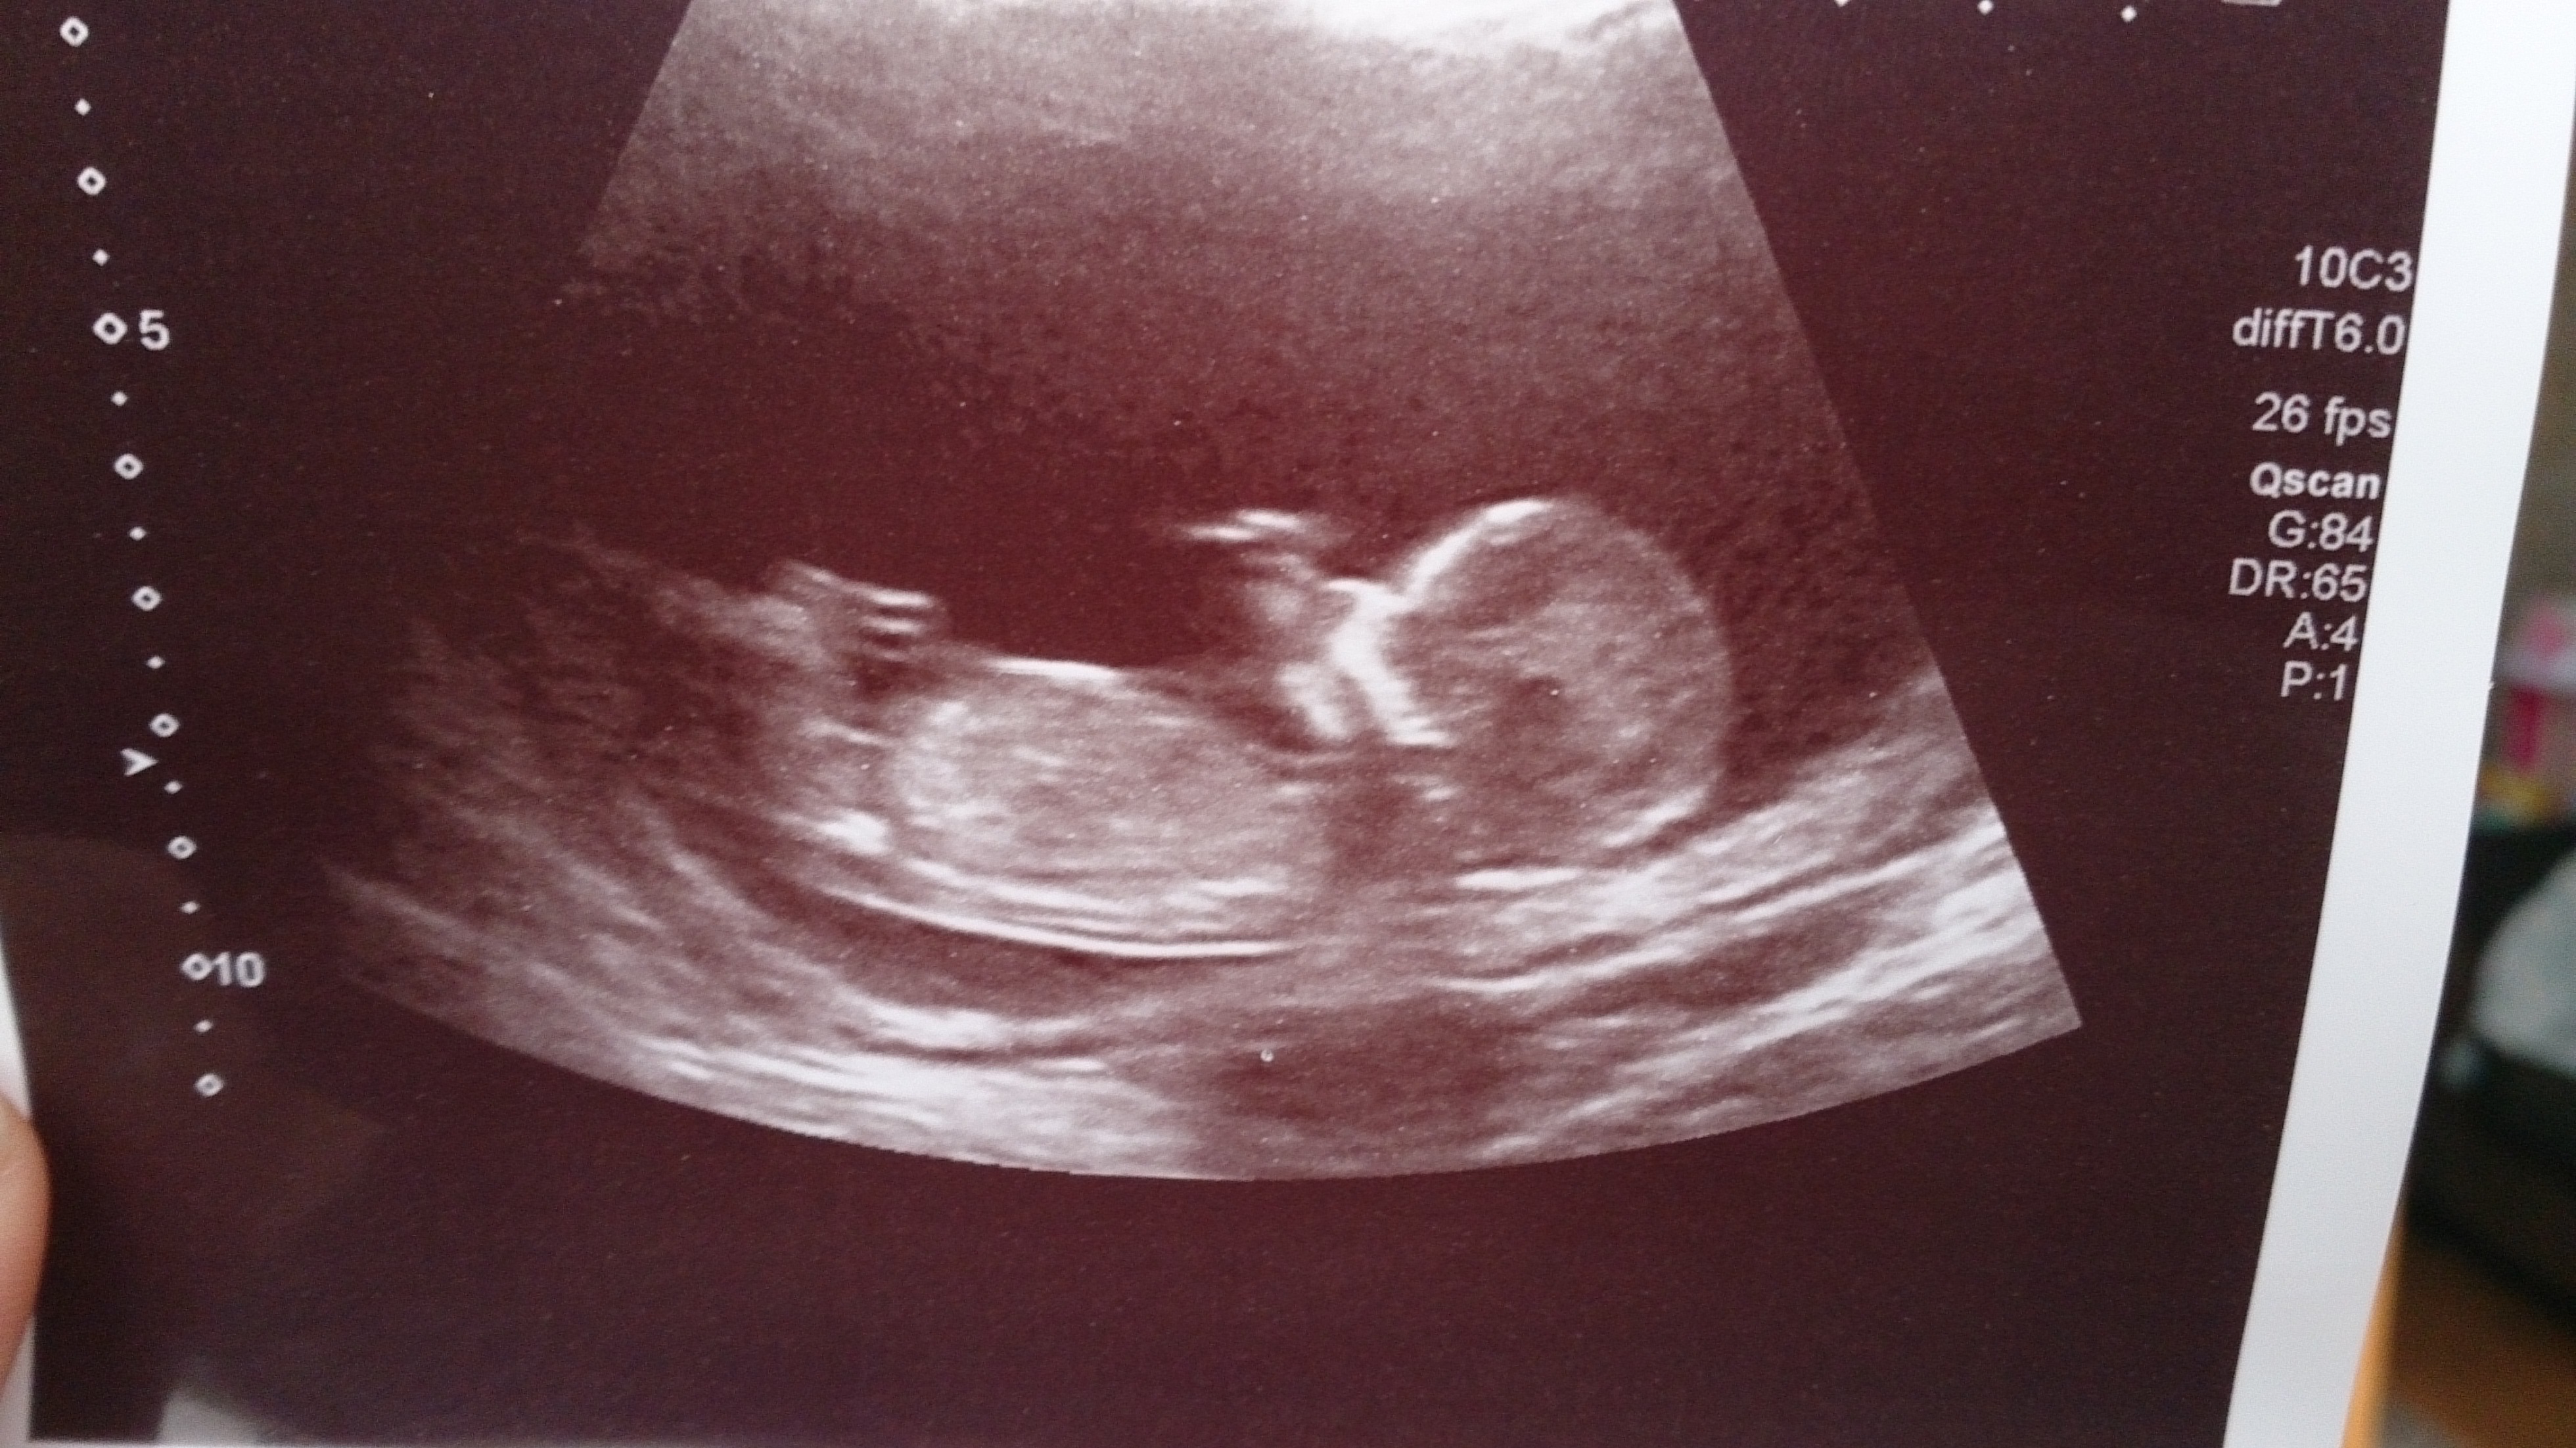

Please can you help me take a guess? We've already a little girl so tried to sway boy but I'm not sure, what do you all think? Thank you in advance xxx

If what I can see in the first pic is the nub, then it's a boy. But the second pic doesn't tell much. Good luck!

Nice stacked nub in first pic. Looks boyish :)